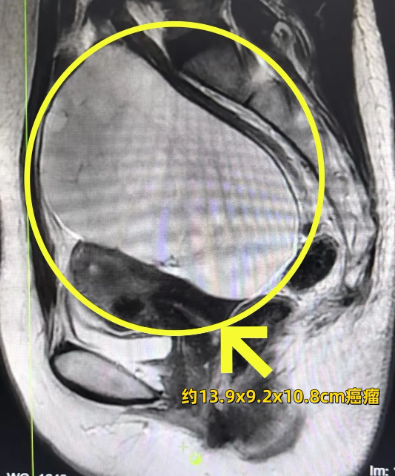

五年後,不斷加重的尿頻、腹部隱脹感讓她無法再忽(hū)視(shì)。10月末,當(dāng)鼓起勇氣的她,找到婦科腫瘤亞專科專家蔡莉,彩超結果卻如晴天霹(pī)靂——盆腔裏曾經的“小囊腫”瘋狂繁殖,已變為直徑13厘米的巨大包塊!

手術台上,殘酷的現實被快(kuài)速病理結果又一次驗證:卵巢癌。蔡(cài)莉(lì)主任立即為其實(shí)施了卵巢癌分期手術。術後病理顯示為(wéi)“卵巢粘液性腫瘤”。